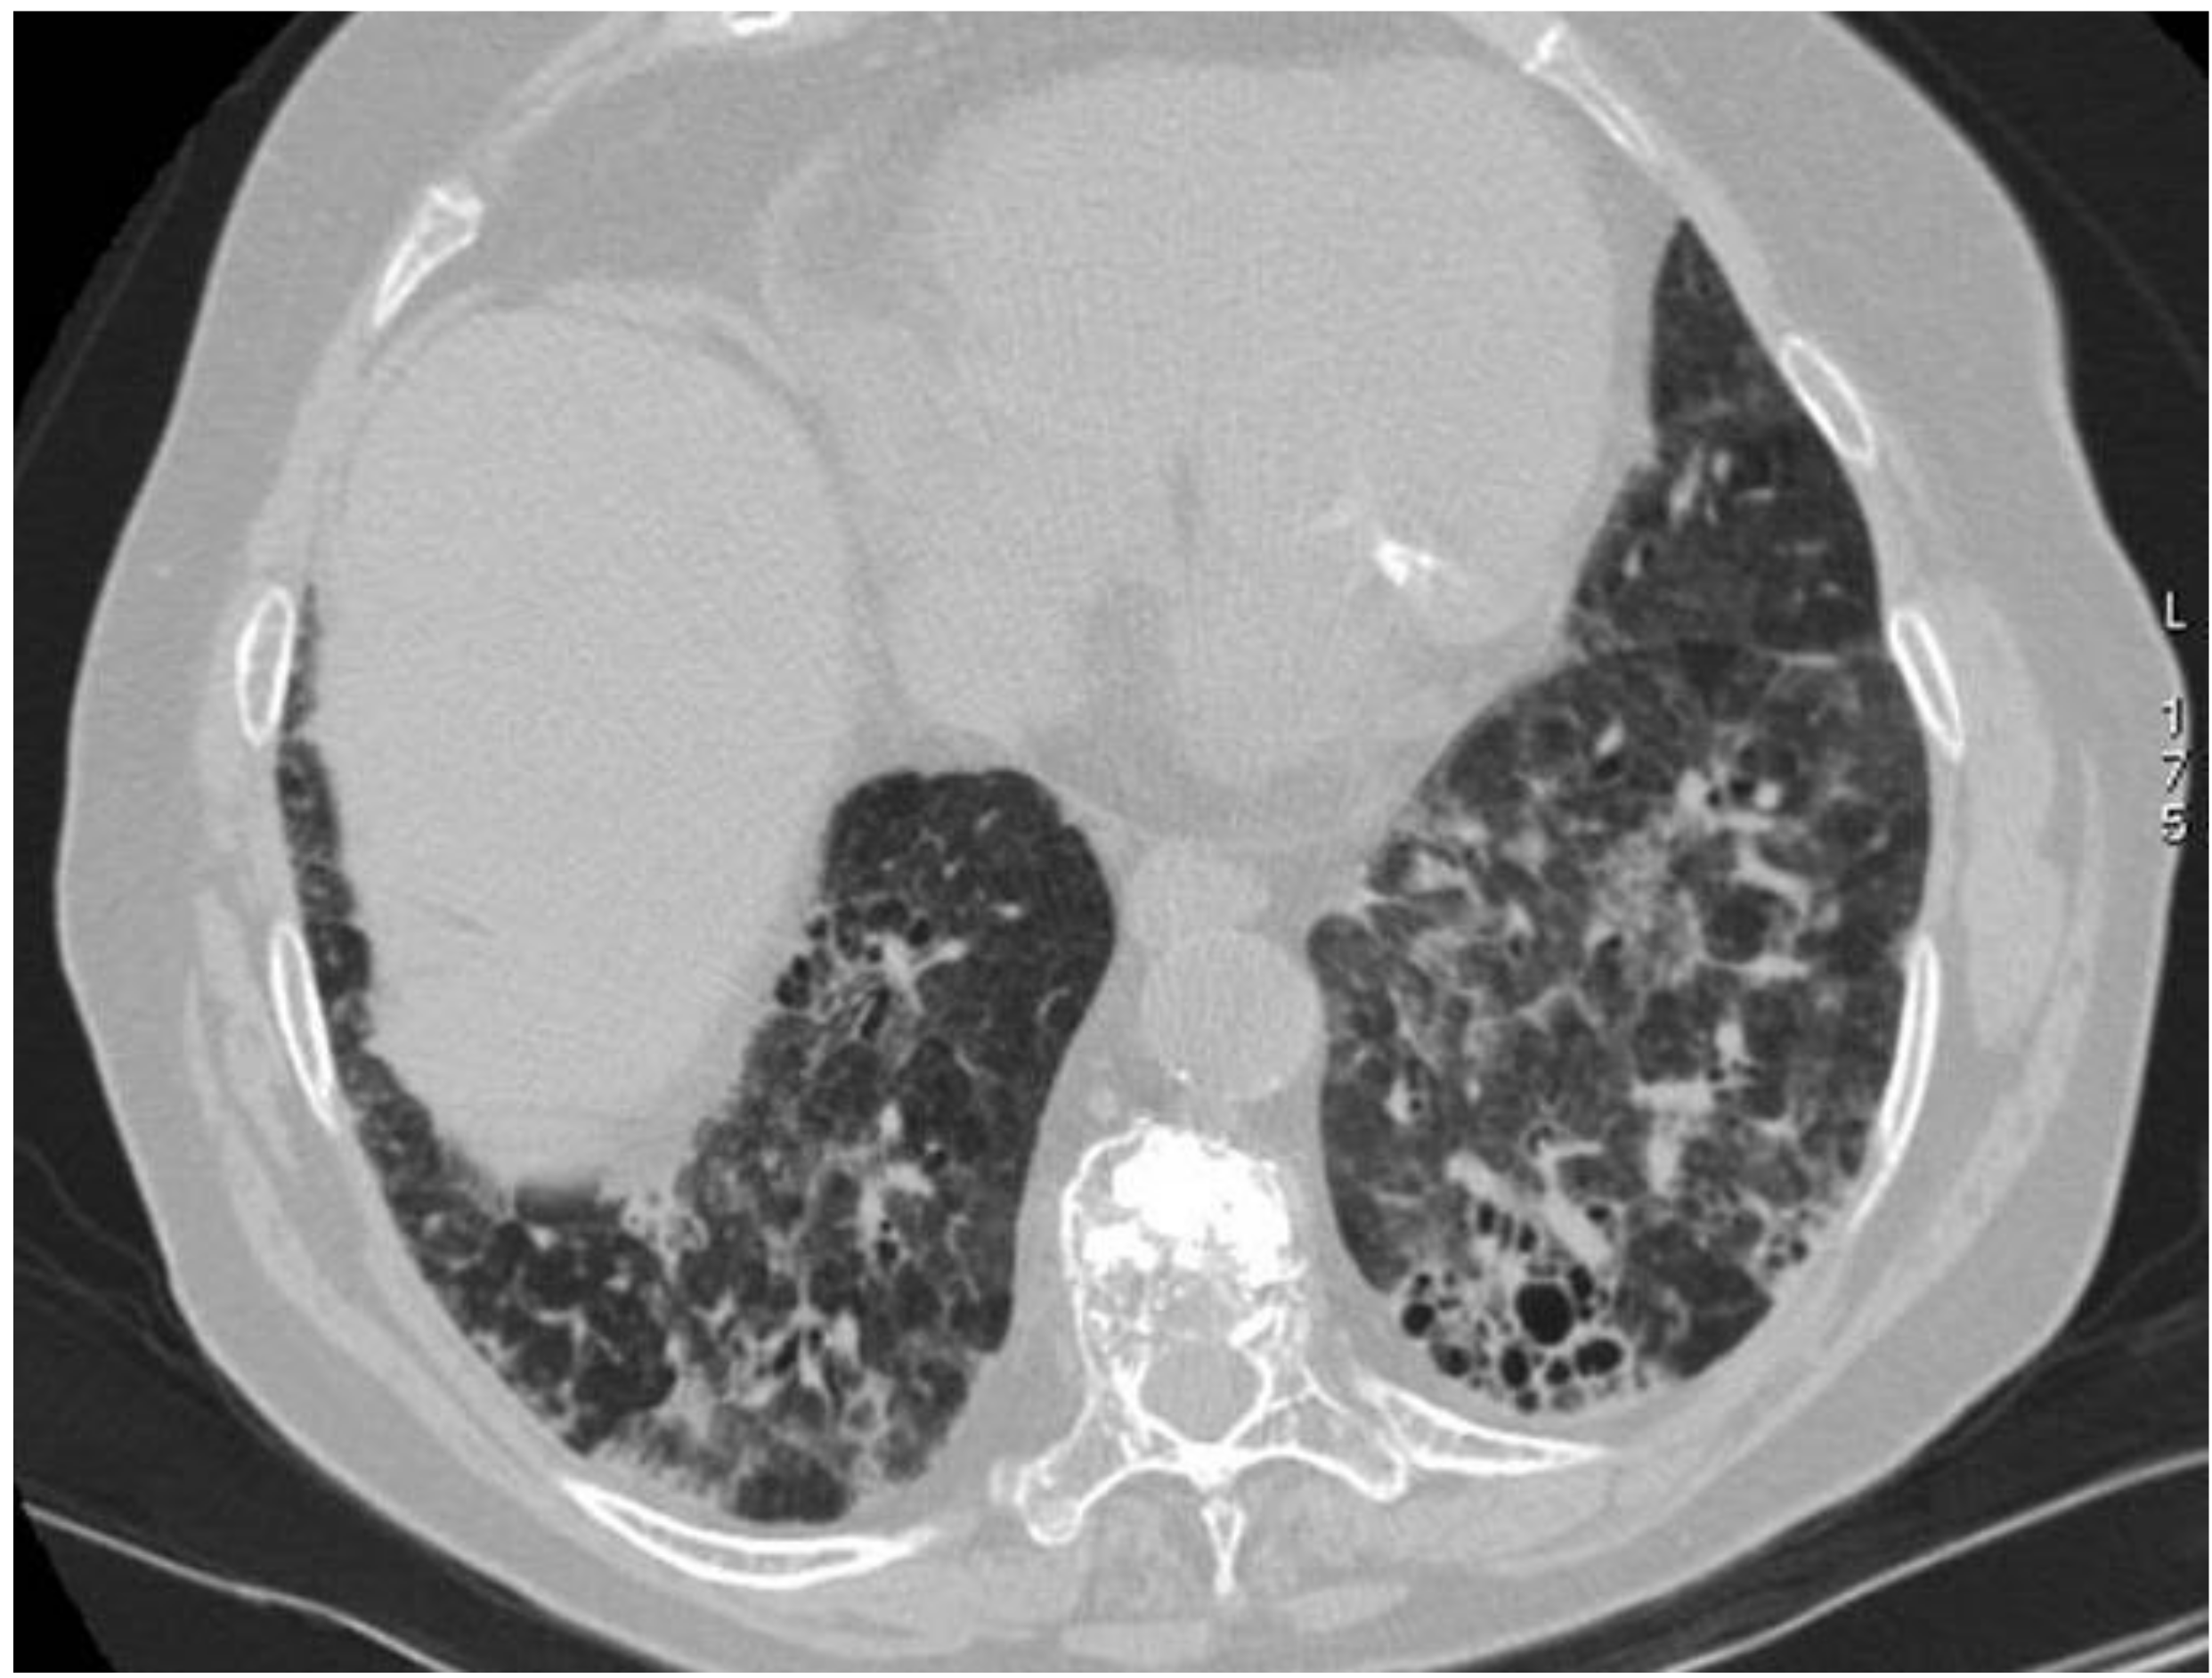

2.3. Microscopic Polyangiitis (MPA)

| MPA | GGOs due to hemorrhagic alveolitis (common); consolidation, nodules with centrilobular distribution (less common) |